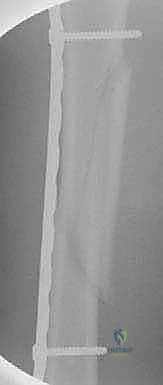

Step-by-Step Surgical Approach and Fixation Technique

Clinical & Radiographic Imaging Archive